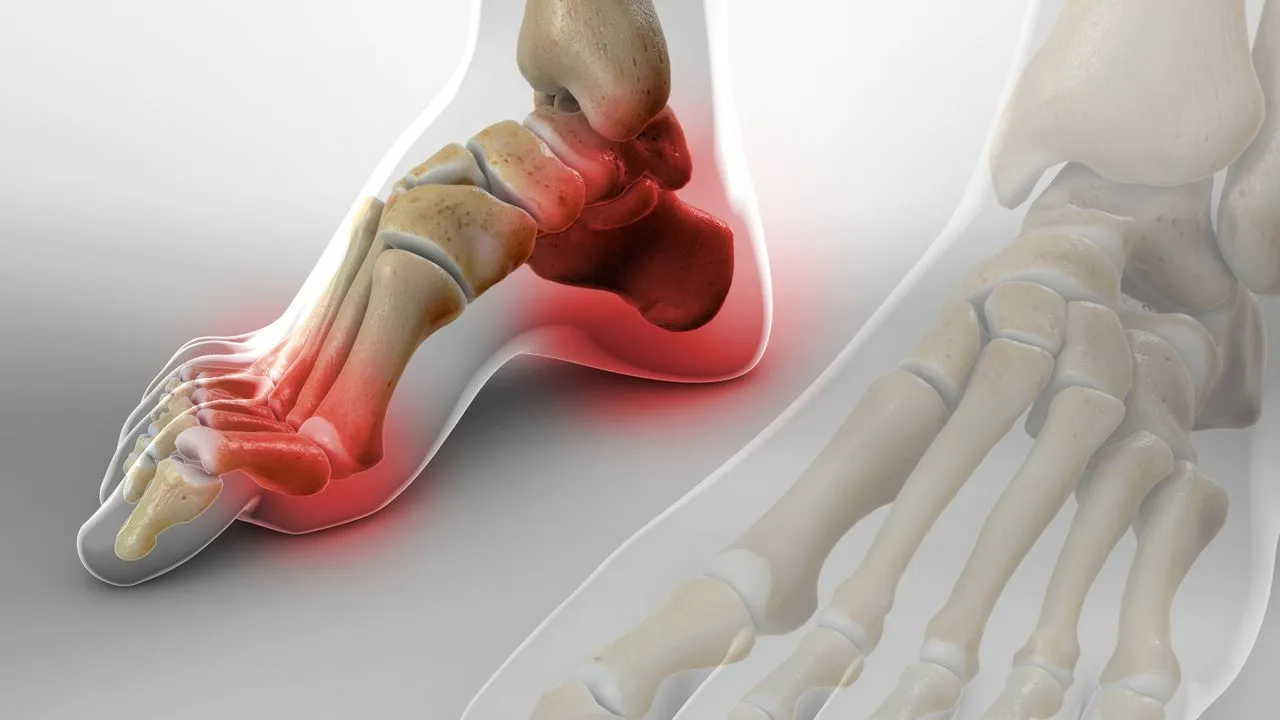

Esporões do Calcâneo

O esporão do calcâneo é uma projeção óssea que se forma no osso do calcanhar (calcâneo), geralmente na sua face inferior, causada por um crescimento anormal de cálcio devido a sobrecarga ou irritação contínua da região. Esta condição está frequentemente associada à fascite plantar, uma inflamação da fáscia plantar que provoca dor na planta do pé.

- Causas comuns:

- Sobrecarga repetitiva no calcanhar (ex: corrida, longos períodos em pé)

- Alterações biomecânicas do pé

- Uso de calçado inadequado, pouco amortecido

- Excesso de peso corporal

- Envelhecimento natural e desgaste dos tecidos

- Tratamento:

- Descanso e redução da atividade física que agrava a dor

- Uso de palmilhas para amortecimento e correção biomecânica

- Exercícios de alongamento da fáscia plantar e tendão de Aquiles

- Em casos persistentes, terapias como fisioterapia, ondas de choque ou até cirurgia podem ser consideradas